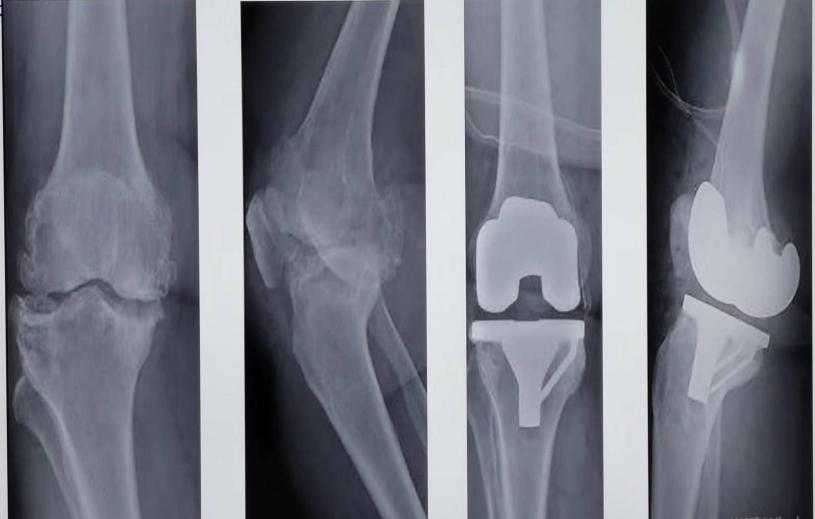

膝关节骨性关节炎

在中国50岁以上人群中,膝关节炎(OA)患病率达14.3%,是老年人致残的主要原因。迄今OA病因尚不明确,但其发生与年龄、肥胖、创伤、剧烈运动及遗传因素等有关。OA最显著的是它对关节软骨的影响,在疾病的发展过程中,关节软骨严重退化甚至缺损。近年来,固原地区膝关节炎老年患者逐年增多,膝关节疼痛困扰人们的日常生活。当下X陷检查为OA明确临床诊断的“金标准”,作为首选的影像学检查。在X线片上OA的三大典型表现为受累关节非对称性关节间隙变窄、软骨下骨硬化和(或)囊性变、关节边缘骨赘形成。根据X线改变Kellgren@lawrence分级:0级:无改变(正常),Ⅰ级:轻微骨赘;Ⅱ级:明显骨赘,但未累及关节间隙;Ⅲ级:关节间隙中度狭窄;Ⅳ级:关节间隙明显变窄,软骨下骨硬化。我科遵循膝关节炎阶梯化诊疗方案,开展了一系列针对于每个病患的个体化治疗。尤其对于终末期膝关节OA开展了重建治疗(膝关节置换术)。